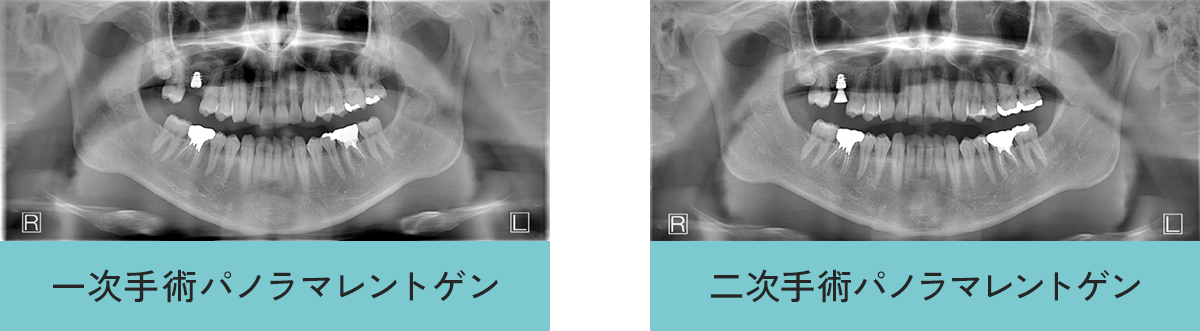

インプラント症例

- 年齢・性別

- 30代男性

- 主訴

- 右上奥が痛む

- 診断名

- 右上奥歯(第1大臼歯)重度う蝕(虫歯)のため保存不可能

- 治療内容

- 重度虫歯の右上奥歯を、抜歯後、骨ができてからインプラント治療を行う。

- 治療期間

- 約1年

- 治療費用

- 総額558000円(税込)

・インプラント治療498000円 【埋入(インプラント入れること)、上部構造 被せ物)含む】

・ソケットリフト50000円 - リスク